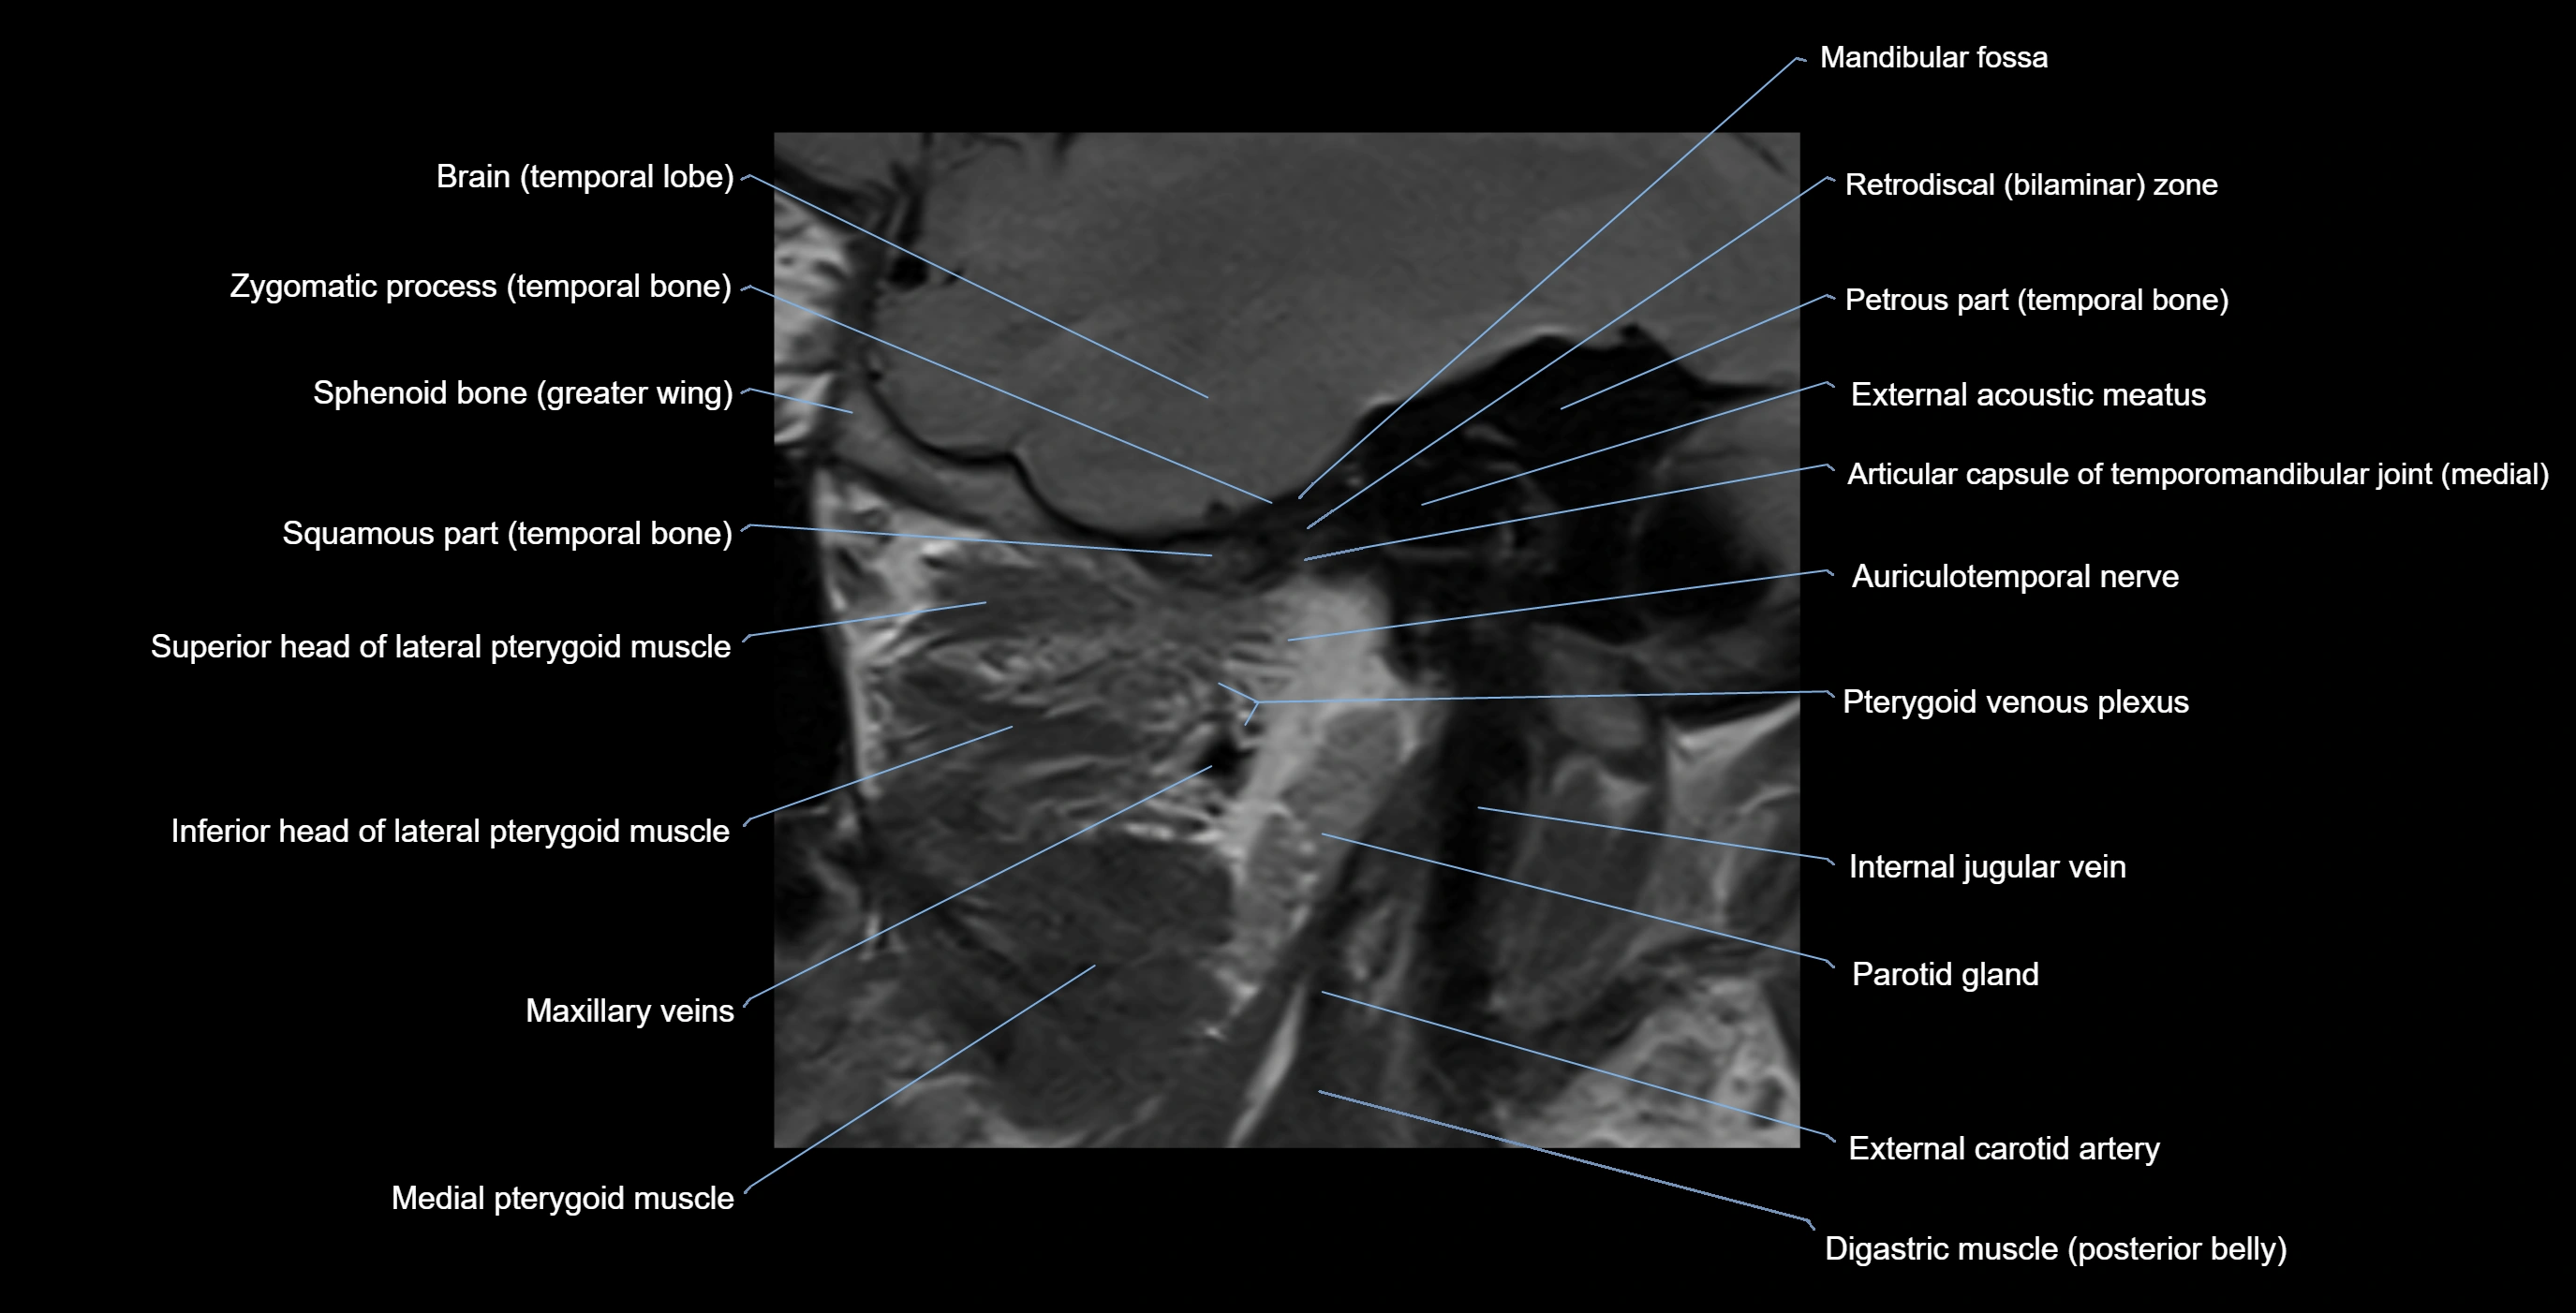

MRI appearance

T1-weighted images:

• Cortical bone: Low signal intensity

• Cancellous marrow: Intermediate to high signal depending on fatty content

• Teeth: Signal void structures

• Adjacent soft tissues: Normal gingiva and oral mucosa signal

T2-weighted images:

• Cortical bone and teeth: Low signal

• Marrow: Intermediate signal